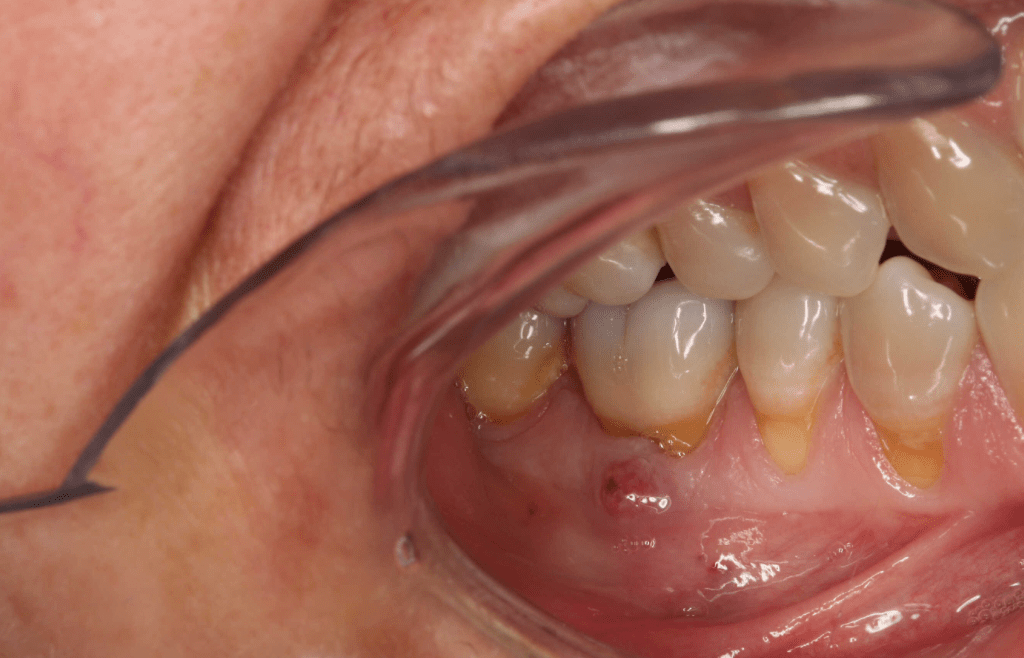

Diagnóstico de fisuras y fracturas

Diente fisurado regeneración total

Diente fisurado, no tratable

Diente fisurado tratable

Diente fisurado tratable con endodoncia

Diente fisurado tratable endodoncia 2

Fisura, remoción amalgama para explorar

Fractura cuspídea tratable

Vertical root fracture